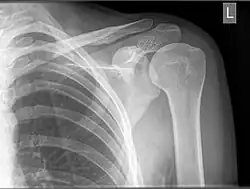

Ze względu na naturę zdjęcia, które jest rzutem obiektu trójwymiarowego na płaszczyznę, a ponadto można je oglądać i z jednej i z drugiej strony, pojawia się problem z rozróżnieniem, z której strony należy patrzeć na zdjęcie. W tym celu w obszarze robionego zdjęcia umieszcza się szablon z niesymetryczną literką (taką, którą można odczytać tylko w jednej pozycji), najczęściej L, P lub R. Litery te oznaczają strony (odpowiednio: lewa, prawa, ang. right) badanego obiektu. Czasem używa się skrótów łacińskich Sin (manus sinistra – strona lewa) i Dx (manus dextra – strona prawa). Znaczniki strony lewej są czworokątne i czerwone (koloru nie widać na zdjęciu), a strony prawej okrągłe i zielone.

Zdjęcie stawu ramiennego